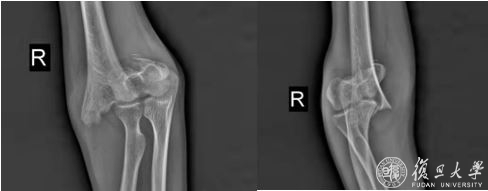

5月21日,云南省大理白族自治州漾濞县发生6.4级地震,距离震中心43公里的永平县震感强烈,在永平县高平外国语学校上学的一名初一学生在此次地震中右肘部损伤伴疼痛活动受限,送入永平县人民医院急诊,拍片发现右肱骨髁上粉碎性骨折,临时复位石膏托固定后,收入永平县人民医院外二科,打算等肿胀消退以后进一步手术治疗。

上午十点,患儿推入手术室,由于右肱骨髁骨折呈粉碎性,错位明显,骨折块碎小,一旦复位不理想,会导致患者今后肘关节畸形愈合,严重影响关节功能,这给手术团队带来了很大的挑战。蔡国平和医疗队队员们、当地医院医生穿着厚重的铅衣透视,力求最小的代价获得完美的复位效果,手术在紧张、有条不紊地按着既定方案进行,最终,患者的骨折获得满意的复位并固定,手术顺利结束。术后,蔡国平和医疗队队员们的手术衣已经湿透,但是脸上却洋溢着手术成功后的笑容。